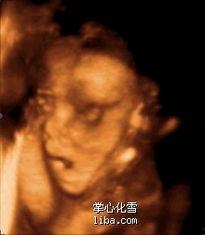

大排畸,全称是大型超声检查,是孕期中非常重要的一项检查。通过高清的超声设备,医生可以清晰地看到宝宝在妈妈肚子里的样子,甚至能捕捉到宝宝的一举一动。对于准妈妈们来说,这无疑是一场视觉盛宴。

想象当你躺在检查床上,医生将探头轻轻放在你的肚子上,屏幕上立刻出现了一个小小的身影。那是一个正在踢腿、挥动手臂的小生命,他的每一个动作都充满了生命力。这时,你的心情是不是也跟着激动起来?

大排畸不仅仅是一场视觉盛宴,更是一次揭秘宝宝成长轨迹的机会。在这个过程中,医生会仔细观察宝宝的心脏、大脑、四肢、脊柱等各个部位,确保宝宝的健康。